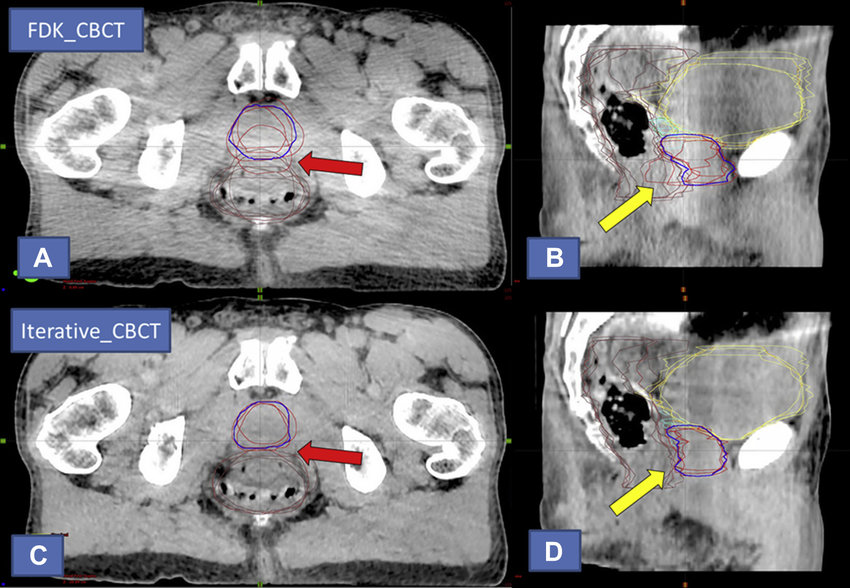

what can kV/kV imaging be matched to?

bony anatomy only

what is the prostate bed shift action level

half of the PTV margin (1 cm) = 5 mm

if shift is larger than 5 mm, apply shift

if below, we don’t need to apply

when can shifts be applied without repeat imaging for prostate bed?

when all shifts are below 1 cm (image repeat action level)